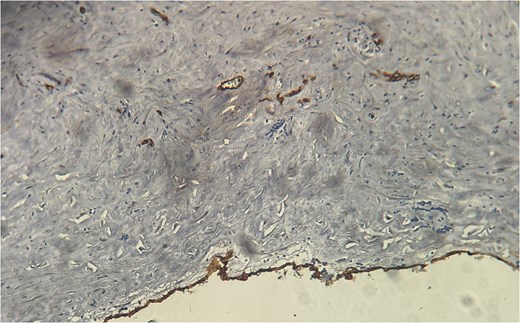

A 60-year-old Moroccan female with no significant medical history presented with chronic periumbilical pain lasting several months, without associated digestive or systemic symptoms, and preserved general condition. Clinical examination revealed periumbilical tenderness. Abdominal ultrasound was unremarkable, prompting an abdominopelvic CT scan, which identified a retroperitoneal inter-aortocaval cystic lesion measuring 86 mm. Surgical exploration revealed a large cystic mass in the mesentery of the small intestine, which was entirely excised. Histopathological examination showed variable-sized cystic cavities with a lymphatic appearance (Fig. 1), lined by flattened and regular endothelium. Some cavities contained pale eosinophilic material interspersed with lymphocytes and areas of red blood cells (Fig. 2). The interstitial tissue exhibited lymphocytic and plasmacytic inflammatory infiltrates. Immunohistochemistry confirmed the lymphatic nature with positivity for Podoplanin/D2–40 (Fig. 3) and CD34 (Fig. 4) and negativity for calretinin (Fig. 5). The patient’s postoperative course was uneventful.

Eosinophilic material and inflammatory infiltrates composed of lymphocytes and red blood cells.